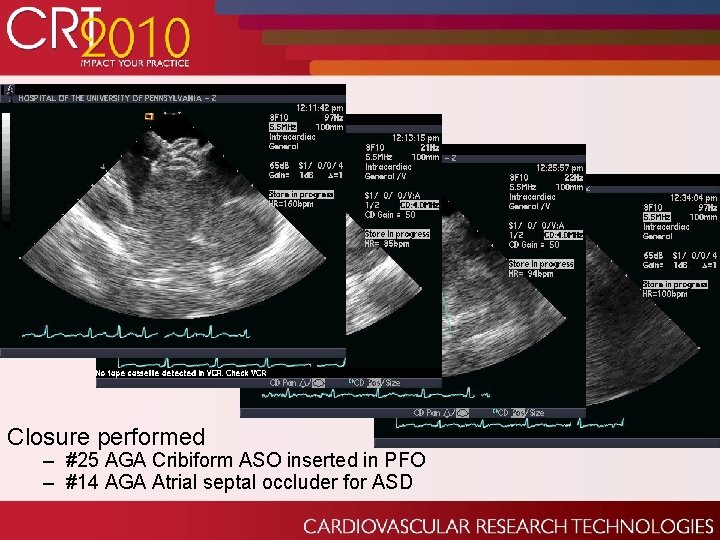

Closure performed – #25 AGA Cribiform ASO inserted in PFO – #14 AGA Atrial septal occluder for ASD